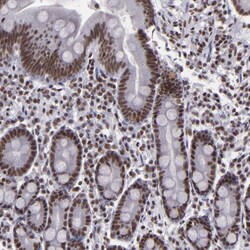

Invitrogen™ BRD8 Polyclonal Antibody

Supplier: Invitrogen™ PA581974

| Immunohistochemistry (Paraffin), Immunocytochemistry | |